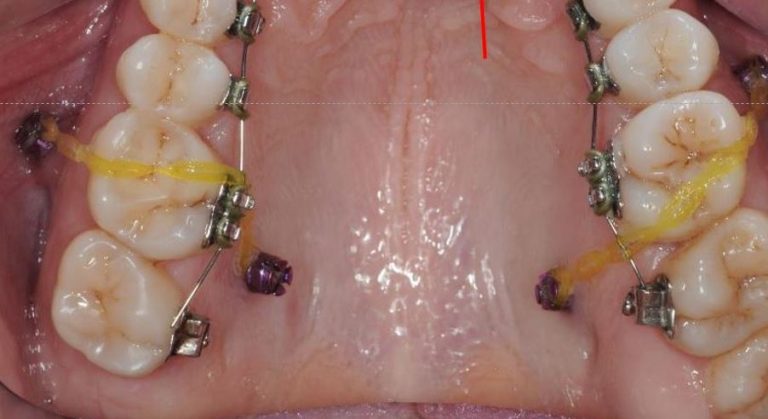

שימוש בכפתורים וגומיות בין לסתיות

לעיתים במהלך הטיפול ישנו צורך בסגירת מנשך פתוח שנובע מעמדה לקויה של הלסתות ו/או השיניים ואינו מאפשר מגע בין השיניים העליונות לשיניים התחתונות, לצורך זה יש לעיתים להרכיב גומיות בין לסתיות שלרוב מעוגנות בכפתורים מהסוג המודגם בתמונות.